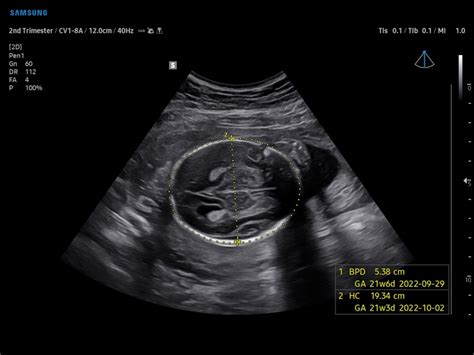

The IIIBPD, or Inner-to-Inner Biparietal Diameter , is a crucial measurement taken during ultrasound scans to assess fetal growth and estimate gestational age. Unlike the more commonly used BPD (Biparietal Diameter) which measures from the outer edge of one parietal bone to the outer edge of the other, the IIIBPD specifically measures the distance between the inner edges of these bones. This subtle difference aims to provide a more accurate and consistent measurement, reducing variability caused by differing skull thicknesses. Doctors and sonographers use this measurement to get a sense of how the baby’s head is developing, which is a key indicator of overall growth and neurological development. So why is this measurement so important? For starters, it helps confirm the estimated due date. The IIIBPD, when combined with other biometric measurements like HC, AC, and FL, paints a comprehensive picture of fetal development. If the IIIBPD falls outside the normal range for a particular gestational age, it could signal potential issues that need further investigation. These issues might include variations in head size, which could be related to genetic factors or other underlying conditions. However, it’s essential to remember that a single measurement outside the normal range doesn’t automatically indicate a problem. Doctors consider the overall growth pattern and other factors before making any conclusions. Regular monitoring and follow-up scans are often recommended to track the baby’s growth trajectory. In summary, the IIIBPD is a vital tool in fetal biometry, providing valuable information about fetal head growth and helping to ensure a healthy pregnancy. Its precise measurement technique minimizes variability, offering a more reliable assessment of fetal development. Remember, guys, that this measurement is just one piece of the puzzle, and your healthcare provider will consider all the information to provide the best possible care.

HC (Head Circumference): Measuring Your Baby’s Head

Head Circumference (HC) is another vital measurement obtained during prenatal ultrasounds. It provides valuable information about your baby’s brain development and overall growth. This measurement is taken around the widest part of the baby’s head and is usually measured in millimeters (mm). The HC is a more reliable indicator of gestational age than BPD, especially in the later stages of pregnancy, because the shape of the head can vary. HC is crucial because it helps healthcare providers assess whether the baby’s head is growing at a normal rate. Significant deviations from the normal range can indicate potential problems. For example, a smaller than expected HC might suggest microcephaly, a condition where the baby’s brain is not developing properly. Conversely, a larger than expected HC could indicate macrocephaly, which may be associated with hydrocephalus (fluid accumulation in the brain) or other conditions. However, it’s essential to remember that these are just possibilities, and further investigations are needed to confirm any concerns. The normal range for HC varies depending on the gestational age of the fetus. Healthcare providers use growth charts to compare the baby’s HC to the expected range for their age. These charts are based on data collected from many pregnancies and provide a reference point for assessing growth. Several factors can influence HC measurements, including genetics, maternal health, and environmental factors. In some cases, a slightly larger or smaller HC may be perfectly normal for a particular baby, reflecting their individual growth pattern. Regular prenatal care and ultrasound monitoring are essential for tracking HC and ensuring that any potential issues are identified and addressed promptly. If your healthcare provider has any concerns about your baby’s HC, they will discuss these with you and recommend any necessary follow-up tests or interventions. Ultimately, the goal is to ensure that your baby is growing and developing healthily. So, while HC is a significant measurement, it’s just one piece of the puzzle. Your healthcare provider will consider all the available information to provide the best possible care. Remember, it’s always best to discuss any concerns you have with your doctor or midwife. They can provide personalized advice and support based on your individual circumstances. Don’t hesitate to ask questions and seek clarification – your peace of mind is essential.